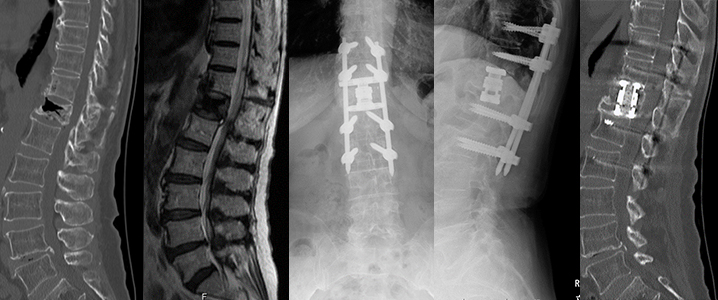

1. 側弯症手術

背中側を切開して椎骨の後方に椎弓根スクリューという金属を挿入して変形を矯正する手術を行います。椎弓根スクリューによる変形矯正は従来の方法に比べ良好な矯正が可能です。ナビゲーションシステムを導入して、正確に椎弓根スクリューを挿入できるように安全対策を行っております。また手術中は常に脊髄に電気を流し、脊髄神経の障害が起きていないかをリアルタイムに確認できる脊髄モニタリングも行いながら手術を行っており、手術治療の安全性はかなり高くなっております。

症例:特発性側弯症